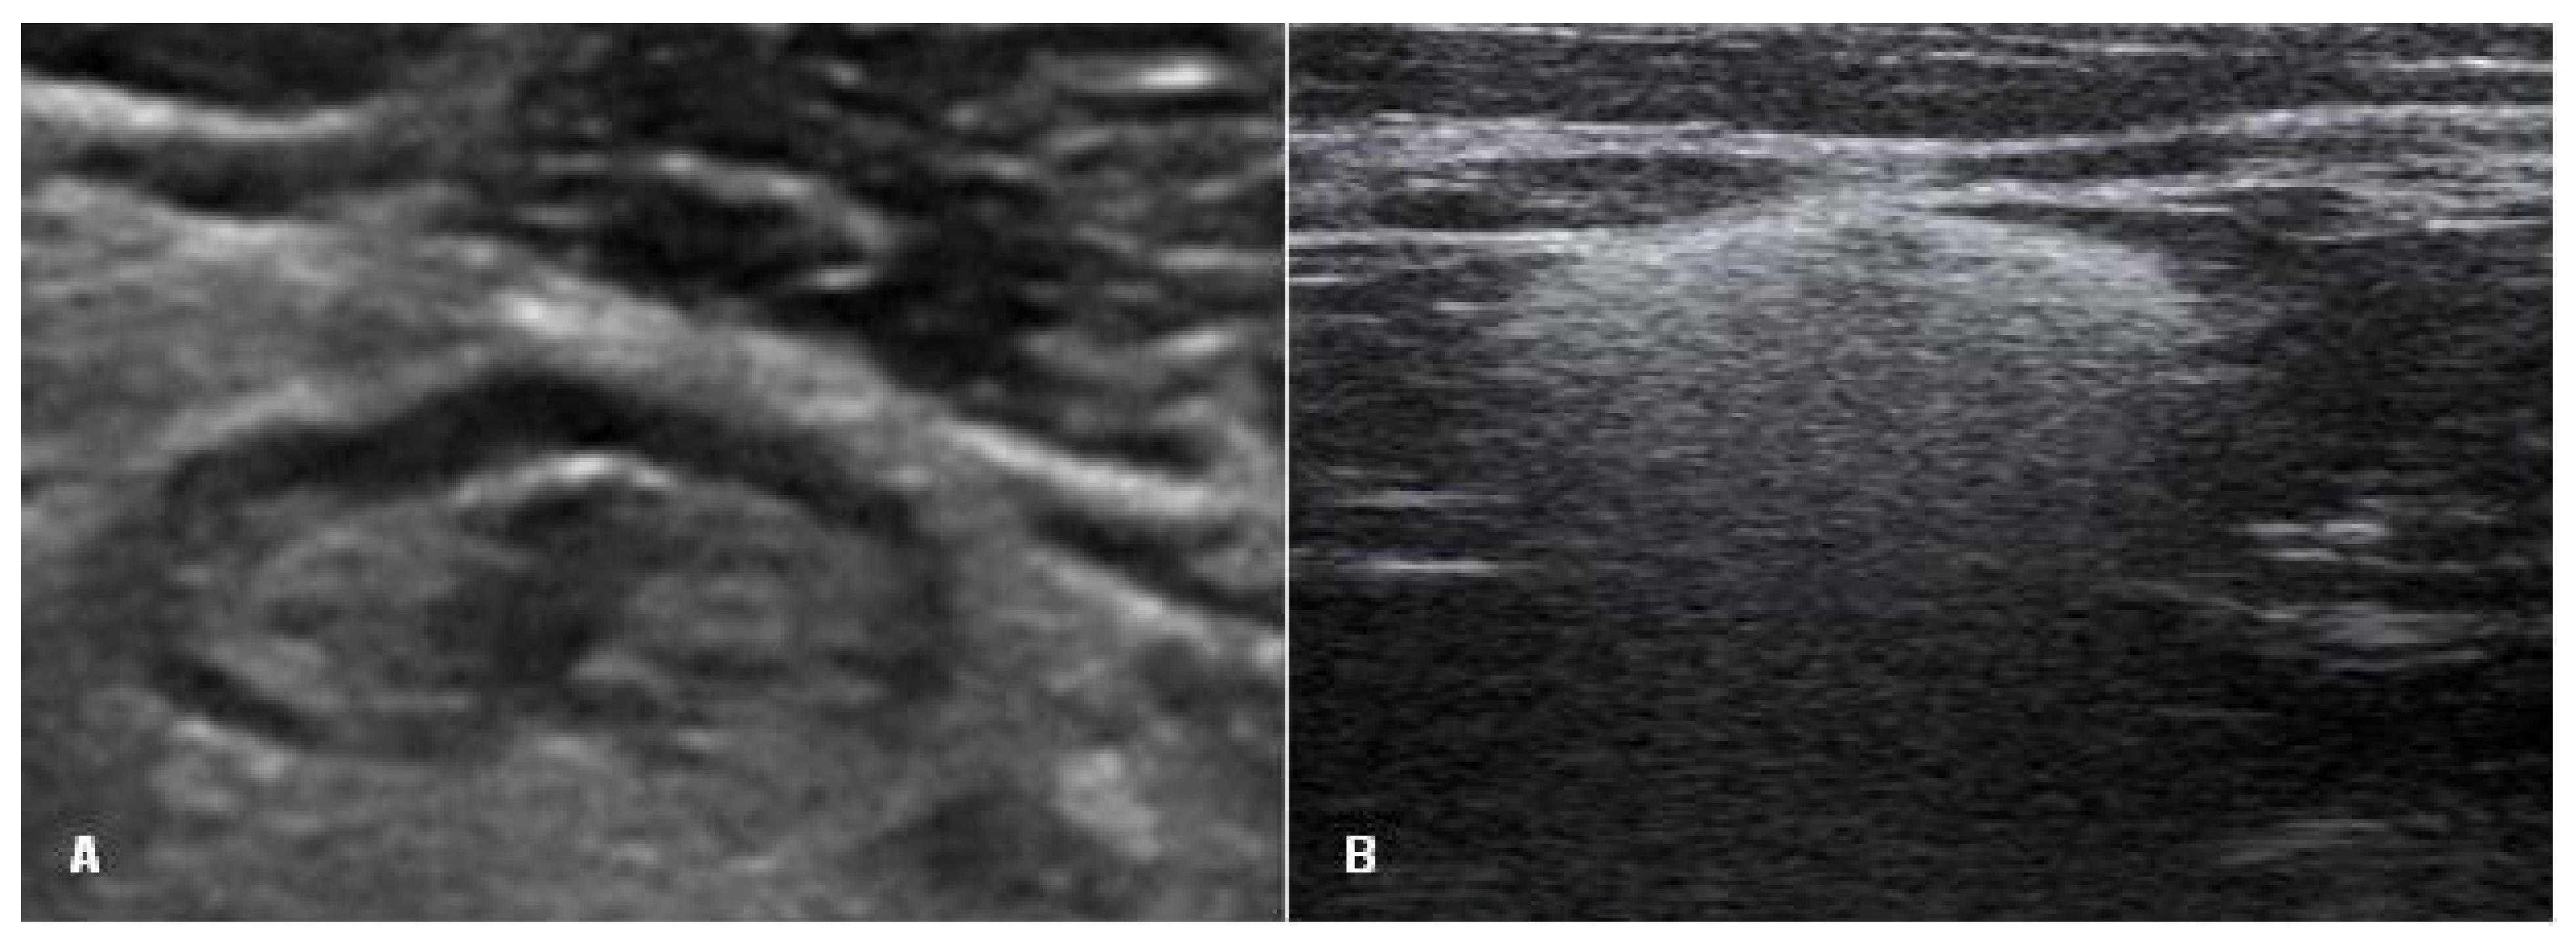

The signs of a ruptured breast implant were an uneven implant shell and inhomogeneous intracapsular echotexture (Figure 2).

Figure 2. Signs of a ruptured implant on ultrasound: white arrow—abnormal shell (one white line is visible); 1—inhomogeneous content.